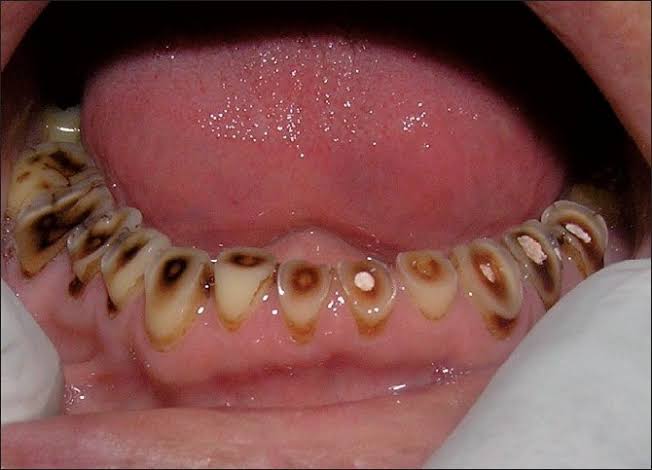

Patient wanted to get a new set of new teeth as old teeth were severely attrited and he was not able to chew. Medical history was taken and patient was fit for all the dental procedure. A detailed radiographic examination was conducted with the help of opg Treatment planning. A detailed case history along with radiological investigation and recording of of Bite of patient it was done in first visit. An appliance to relieve occlusion was given for 21 days Root canal treatment it was perform for all the teeth in subsequent visits. Occlusion was recorded using a specialised semi adjustable articulator. A temporary prosthesis was given to be used for or 15 days. A permanent Restoration was fabricated using pfm Crowns. A patience on patient end is a much needed thing as it involves time duration of of 1 to 2 months. Patient has to be absolutely serious about the treatment protocols which we are following as it involves use of appliances on patients end. Patient has to leave habit of eating Supari and tobacco as it was the cause in in severe reservation and attrition of teeth the artificial prosthesis is a finely crafted instrument that needs to be used with precision. so patients willingness and a positive mindset is Paramount in treating such cases.